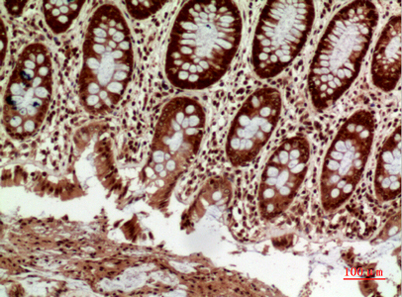

Product name: HLA-DQB1/2 rabbit pAb

Dilutions: Western Blot: 1/500 - 1/2000. IHC-p: 1/100-1/300. ELISA: 1/20000. Not yet tested in other applications.

Immunogen: The antiserum was produced against synthesized peptide derived from the Internal region of human HLA-DQB1/HLA-DQB2. AA range:131-180